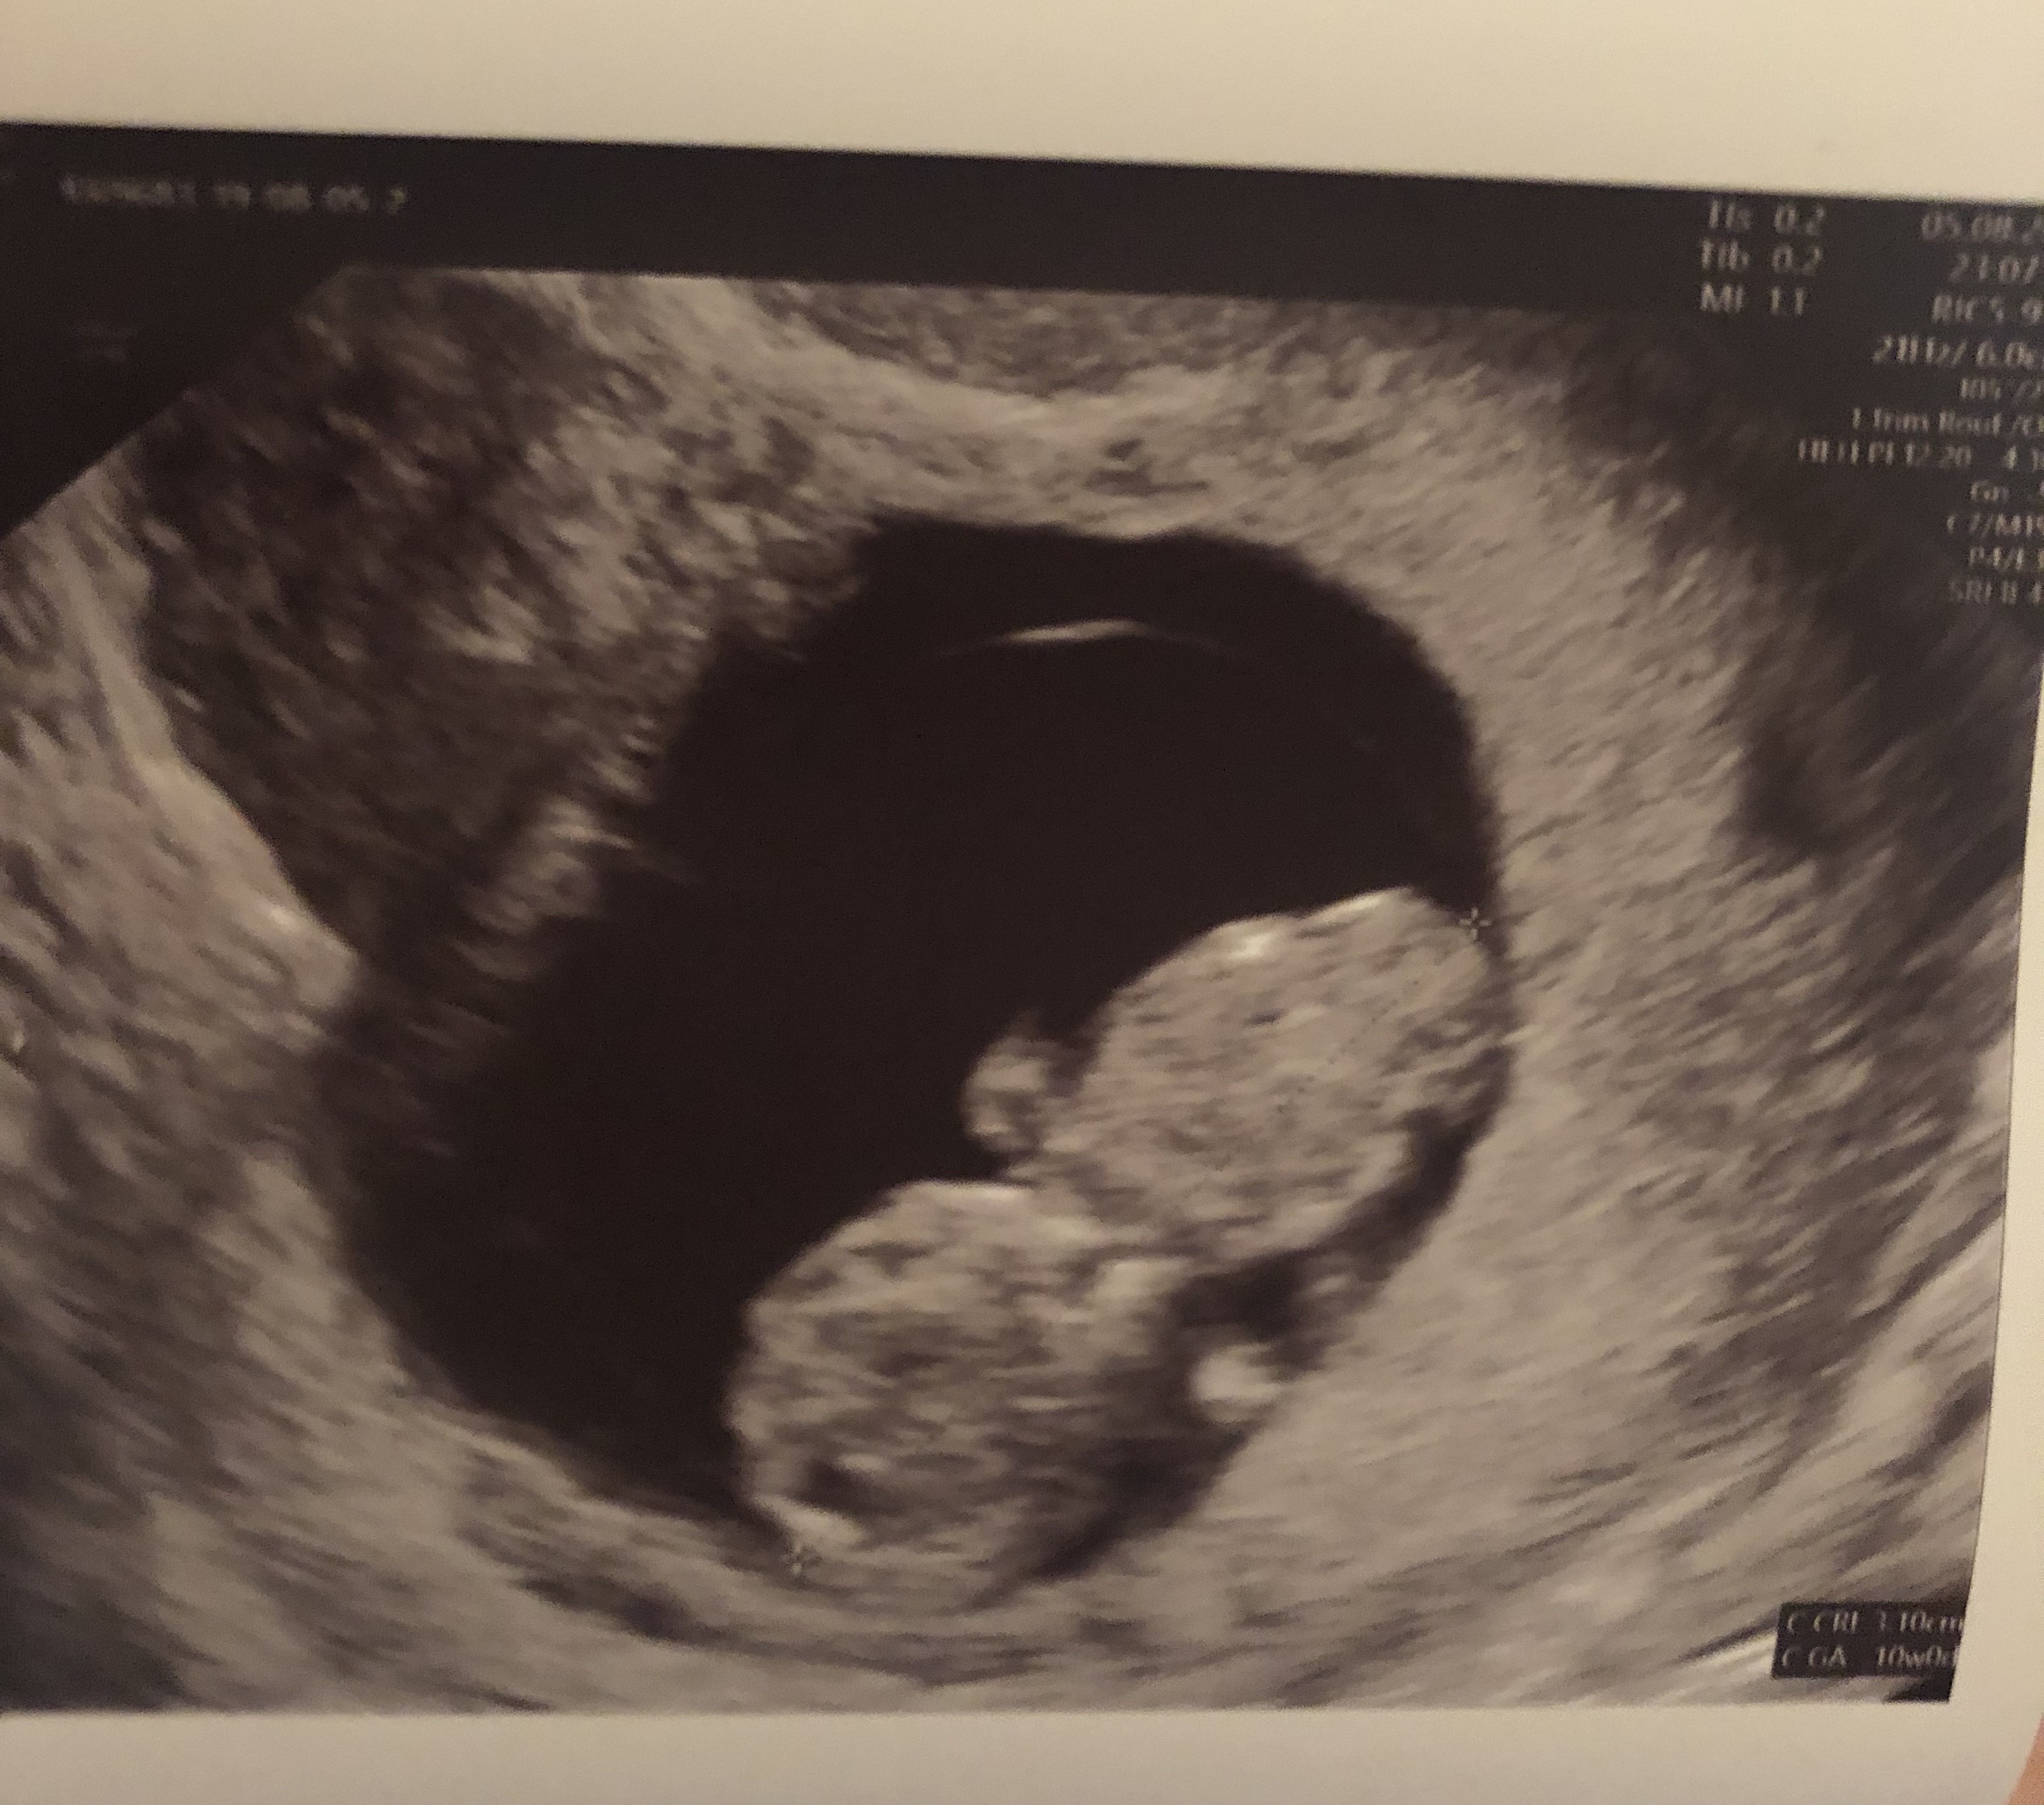

Wróciłam już do domu. Z jednej strony ogromna radość, bo serduszko bije, dzidzia rośnie, a nawet wyprzedza swój wiek wg miesiączki. Ma już 3,1cm i wg usg jest to 10t0d. Super było je zobaczyć chociaż przez pare sekund. Zła wiadomość jest taka, ze krwiak jest dalej... umiejscowienie w miarę „dobre”, ale muszę bezwzględnie cały czas dalej leżeć... no nic trzeba się poświecić, dla dziecka wszystko. Załączam fotki: na jednej dzidzia, a na drugiej z lewej górnej strony widać krwiak.

Jaka śliczna. ...widać główkę i tułów